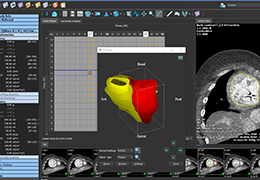

View X-Ray CT & MRI Scans Fast and Easily

Designed for surgeons, Pro Surgical 3D makes it easy to view patient scans quickly. Pro Surgical 3D facilitates the optimal 3D treatment and assessment workflows based on X-ray CT and MRI scans – and best of all, it’s FREE!

Traditional multi-planar slicing

High-quality and fast 3D reconstruction and 3D rendering

Performs 3D reconstruction and volume rendering.

Multi-planar slicing.